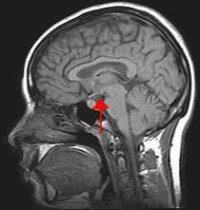

Situación do hipotálamo no cerebro

Científicos canadenses descubriron un mecanismo que podería axudar no tratamento dalgunhas enfermidades relacionadas coa memoria, segundo queda recollido na revista Annals of Neurology. A descuberta ocorreu accidentalmente, cando os expertos estaban a realizar unha exploración cirúrxica no cerebro dun home de 50 anos para intentar reducirlle o apetito e neutralizar a súa crecente obesidade.

En lugar de perder o apetito, o home recordou con exactitude detalles de feitos ocorridos cando tiña 20 anos e as probas posteriores demostraron que aumentara ademais a súa capacidade de aprendizaxe. Cando os médicos estaban a traballar no seu hipotálamo, vinculado coa sensación de fame, o paciente informou de que lle estaban a agolpárselle os recordos na memoria e a medida que se incrementaban os estímulos se ían volvendo máis claros.

Os neurólogos continuaron coas probas durante tres semanas máis, tras o que concluíron que a estimulación do hipotálamo aumentou de forma considerábel a súa capacidade de aprendizaxe. Para os científicos foi unha sorpresa obter estes resultados xa que esta parte do cerebro non está vinculada directamente co proceso da memoria.